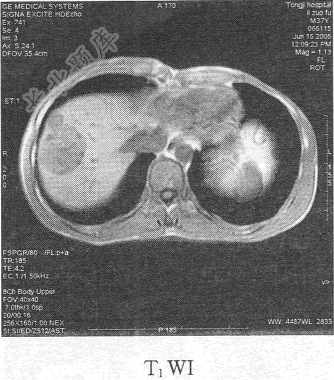

- 单项选择题患者男,54岁。体检发现肝脏占位,MR图像如下,最有可能的诊断是

C、肝血管瘤